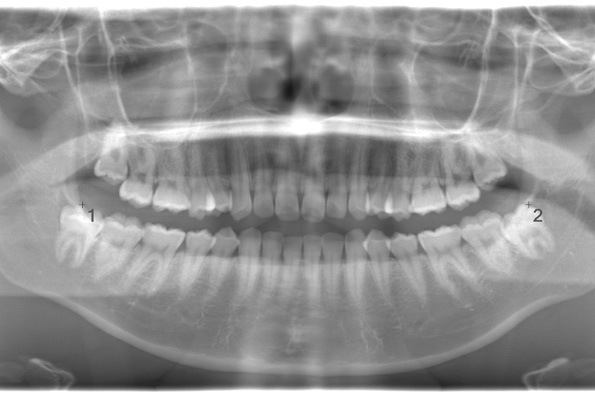

CASE 1

| 年齢・性別 | 30代・女性 |

| 主訴 | 左右に分けて親知らずを抜きたい、できれば痛くなく抜きたい |

| 親知らずのはえ方 | 完全に出ていてまっすぐはえている |

| 抜歯期間 | 15分 |

| 抜歯費用 | 約2,000円(保険内) |

| 抜歯内容 |

何度か虫歯になり痛みはないが早めに抜きたい。 完全に頭が出ているため歯ぐきを切ったり骨を削らずに抜歯しました。 根の形も単純なため抜歯自体は5分もかからず上下ともに終わりました。 術後痛みや腫れも出ていません。 抜歯後は感染をしやすいため必ず抗生物質を飲み切ってください。 |